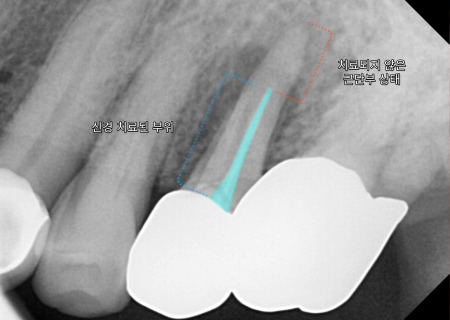

왼쪽 위 작은 어금니 주변으로

거뭇한 뿌리 끝 염증이

확인되는데요.

예전에 신경 치료했던

치아 속으로 탈이 난

모습입니다.

근단부 끝까지

제거 및 충전이

되지 않아 보여

재신경치료(re-endo)를

시도해 볼 수도 있겠지만,

심한 병소로 주변 뼈가

많이 녹아 있는 모습에

자연 치아를 살리기는

무리가 있어 보입니다.

또한 파노라마로

전체적인 입 속 체크를

해 보았을 때,

왼쪽 맨 끝으로 아직

뼈가 덜 아문 흔적이 있습니다.